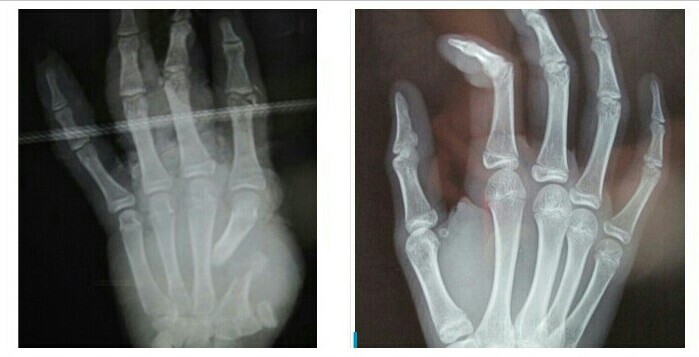

Lelaki dewasa itu tergeletak dengan luka menganga di lutut kanannya, besar sekitar 10 centi dengan tulang menonjol keluar, pecah, dan serat serat otot yg robek tidak beraturan bercampur kerikil, pasir dan potongan rerumput hijau kuning. Darah membasahi celananya yang sengaja digunting oleh petugas. Tidak tampak darah mengalir kencang, bagian ujung kaki teraba hangat dan tidak pucat. Sepertinya pembuluh darah utama kaki kanannya itu aman.

Patah tulang dengan luka terbuka kotor seperti itu hanya salah satu dari sekian hal rutin yang ditemui setiap hari. Patah tulang terbuka dapat menyebabkan infeksi lokal sekitar luka (infected wound) maupun infeksi sistemik (sepsis) . Infeksi sistemik dapat berujung kepada kematian. Infeksi lokal bisa berlanjut lama dan lebih jauh ke dalam tulang, infeksi ini yang disebut sebagai chronic osteomyelitis.

Osteomyelitis kronis termasuk salah satu yang sulit untuk disembuhkan, diperlukan berbagai tindakan termasuk operasi seperti pembersihan (debridemen), membuang nanah yang berada di dalam tulang sekaligus membuang tulang yang mati (sequestrectomy). Bagian jaringan lunak (otot dan sekitarnya) yang terinfeksi dan menjadi jalur keluarnya nanah hingga kulit (sinus track) dibuang. Penanaman cangkok tulang (cancellous bone graft) disertai butir butir antibiotik (antibiotic beads) dilakukan sebagai bagian upaya eradikasi holistik bakteri penyebab osteomyelitis. Sering dijumpai pasien memerlukan berkali-kali operasi disertai pengobatan antibiotik suntik (injeksi) dan minum (oral) dengan jangka lama. Tingkat kambuhan (rekurensi) penderita osteomyelitis cukup tinggi yaitu mencapai 30 %.